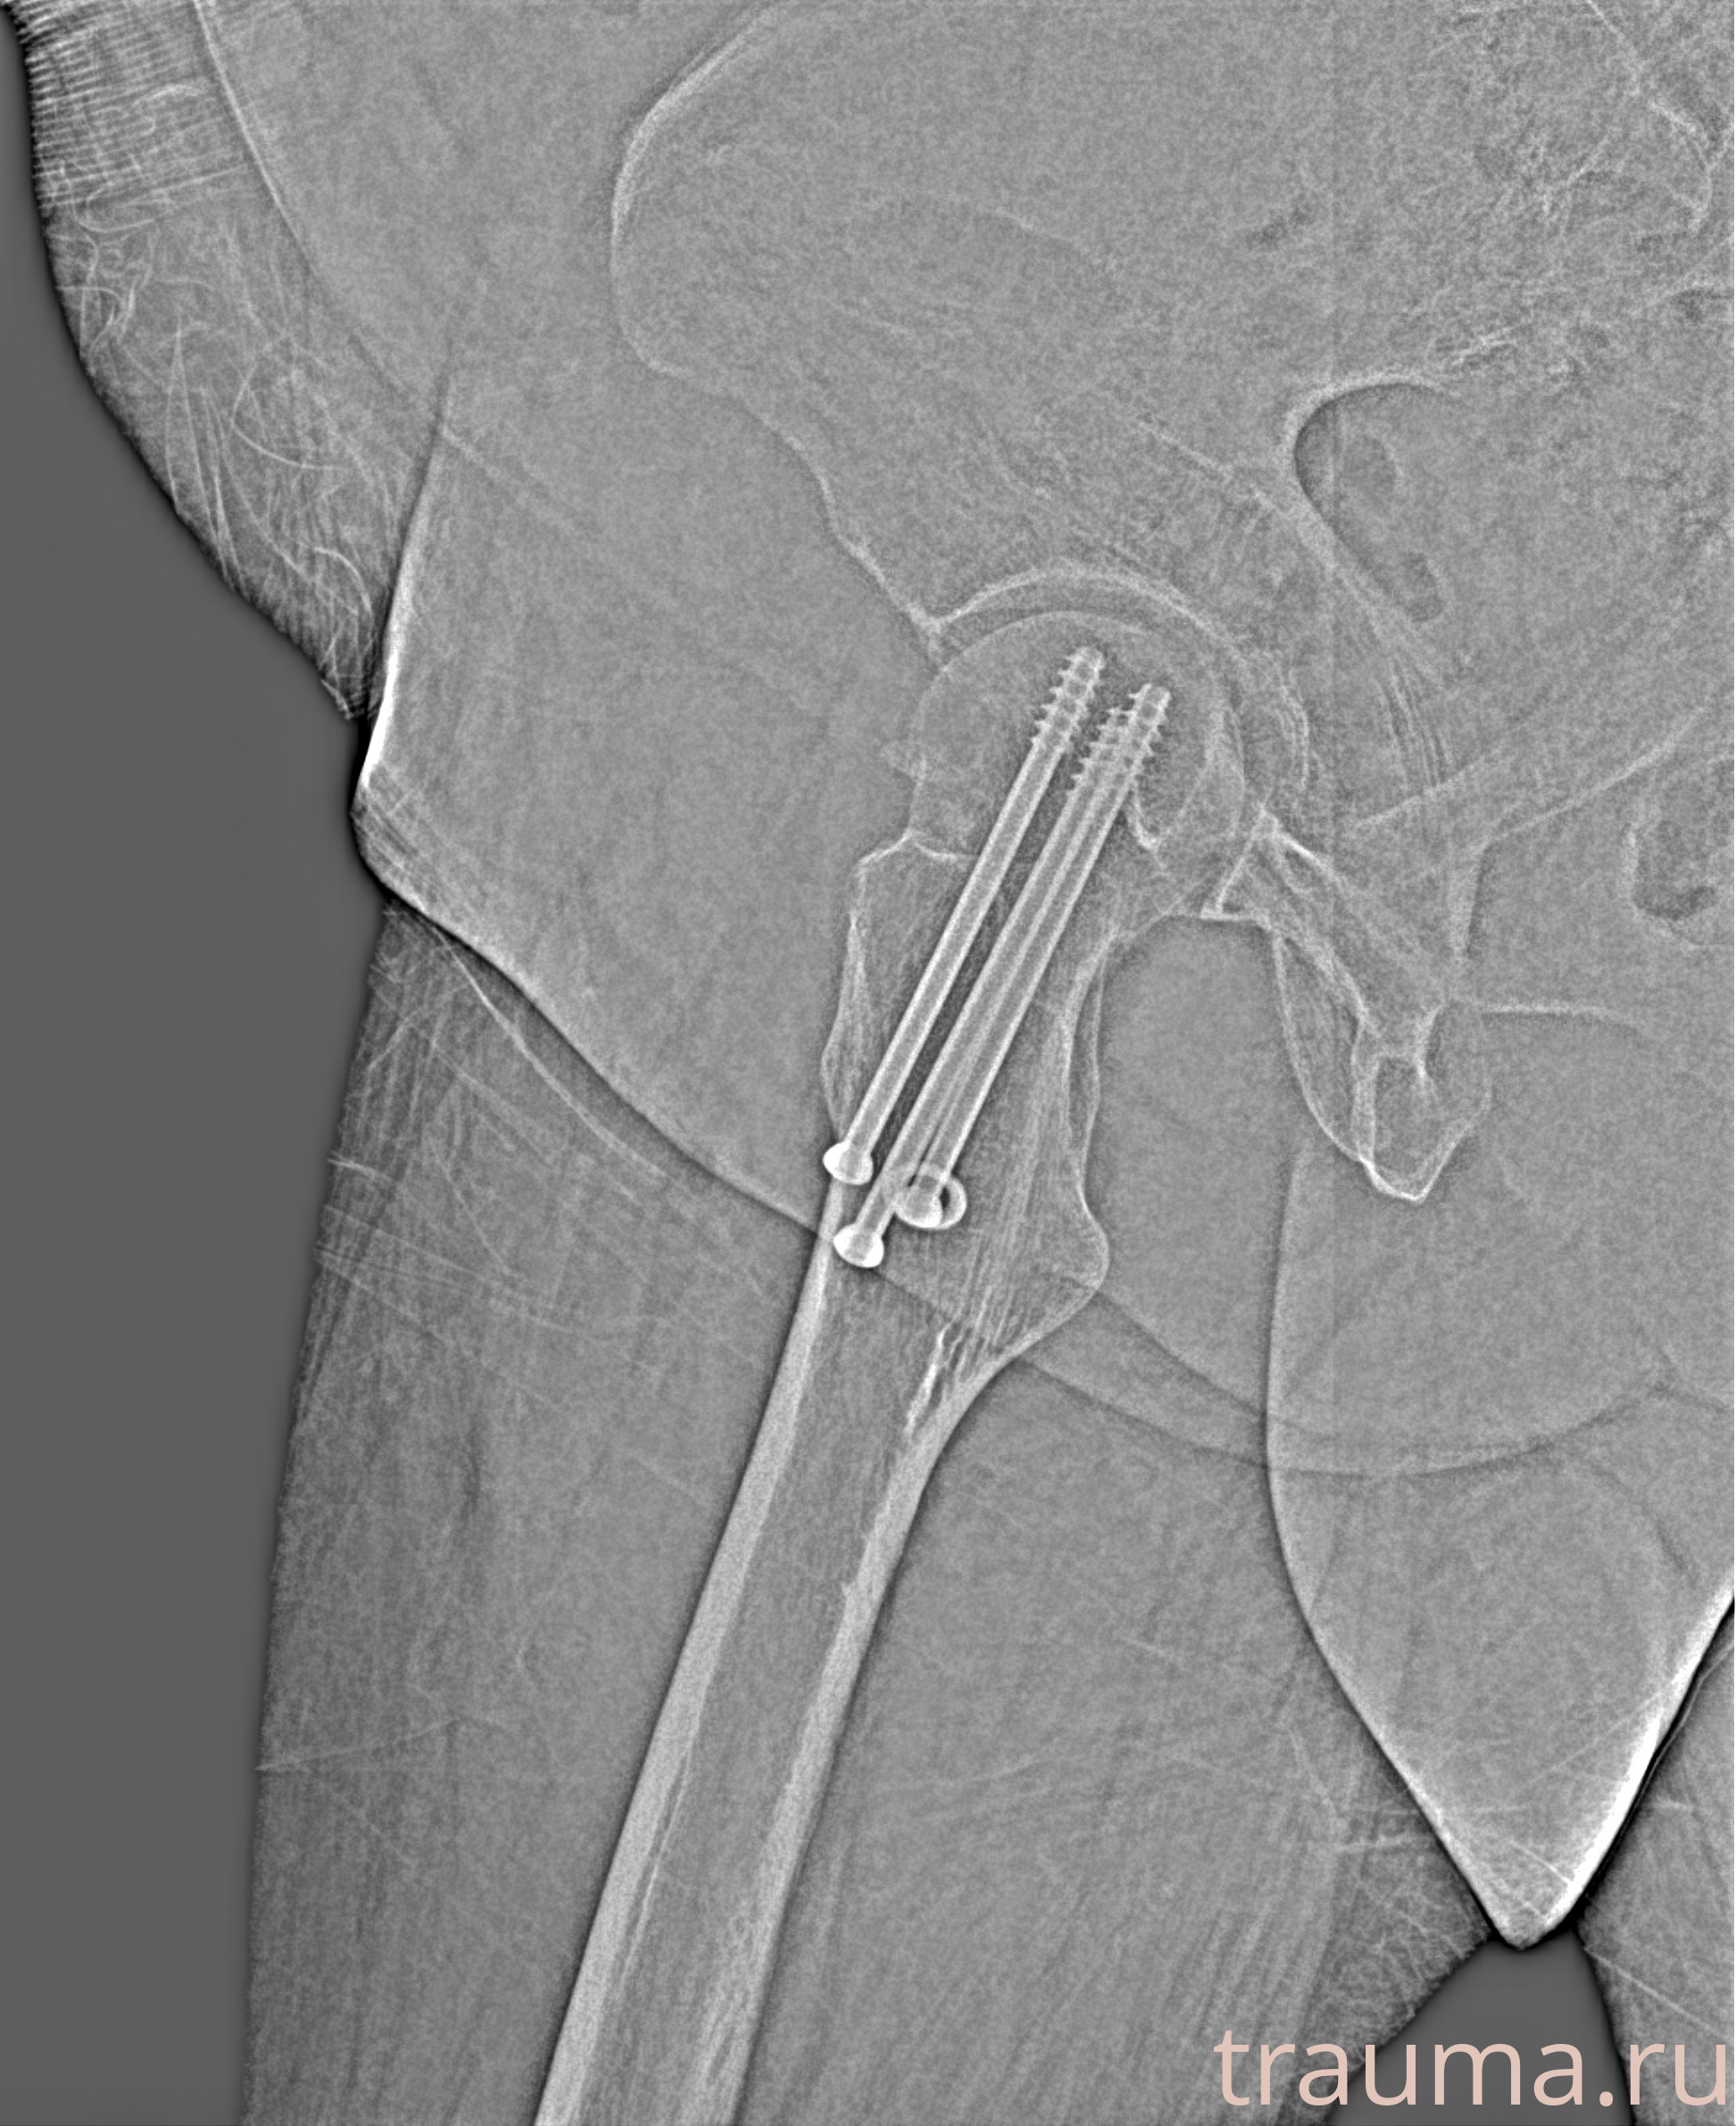

Рентгенограммы

Рентген на дому: по вашему адресу приезжает врач-рентгенолог, травматолог-ортопед с мобильным рентгеновским аппаратом, проводит диагностику травмы или заболевания, делает необходимые рентгенограммы, дает рекомендации по дальнейшему лечению. Получить качественные снимки в домашних условиях возможно благодаря уникальной методике, разработанной МосРентген Центром для института  Склифосовского